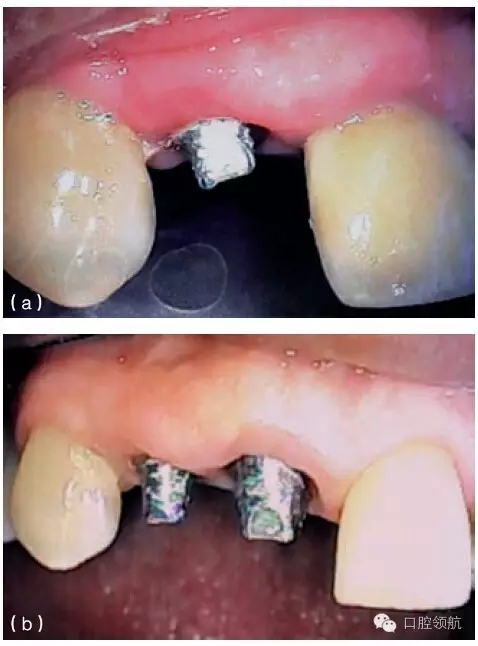

圖9.24 (a) 由于種植體植入前,沒有進(jìn)行充分的位點恢復(fù),最終在修復(fù)體唇面輔以齦色瓷,以彌補軟組織的不足。(b)口內(nèi)全景觀,全口烤瓷熔附金屬修復(fù)體,粘結(jié)固位,注意左側(cè)側(cè)切牙牙齦區(qū)域的齦色瓷。